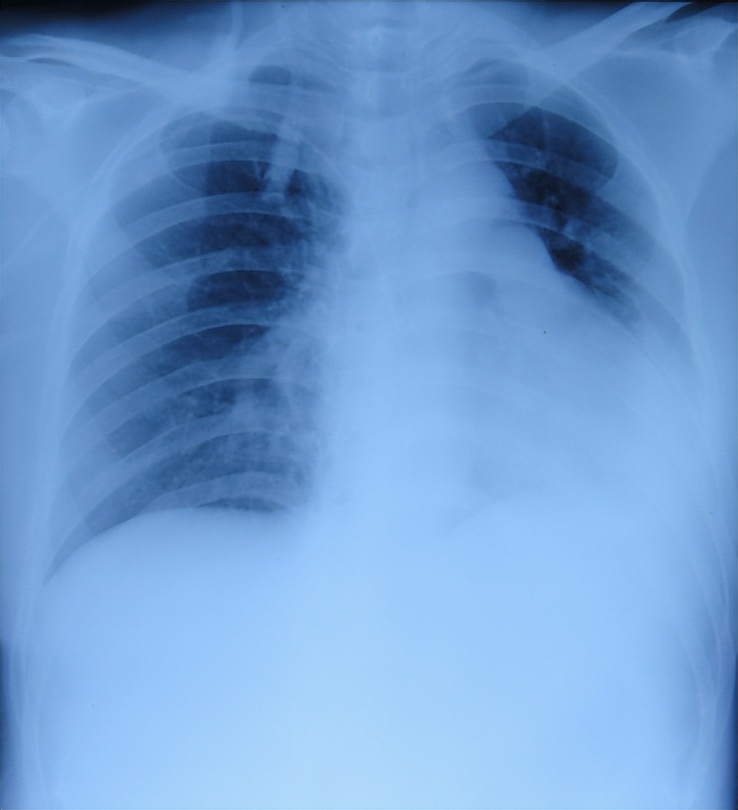

听神经瘤切除术后14天即2013年11月28(腰大池引流术后7天),查肺片(图-4)认为有感染。

图-4:2013年11月28日肺片